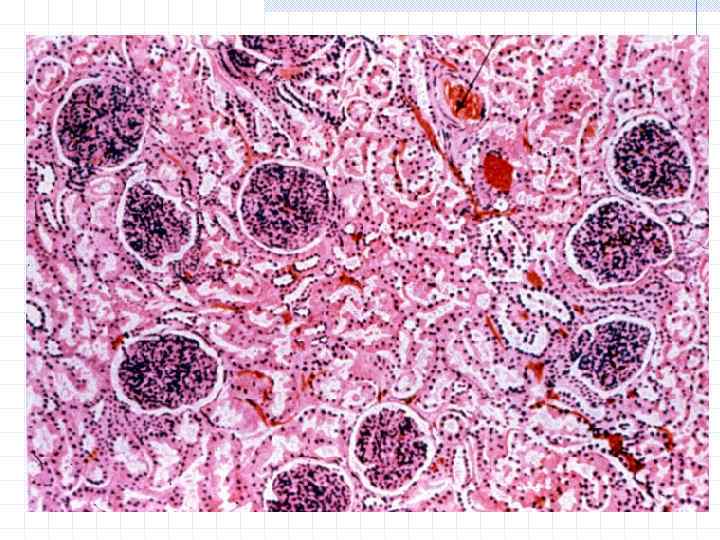

Механизм остро го диффузного гломерулонефрита